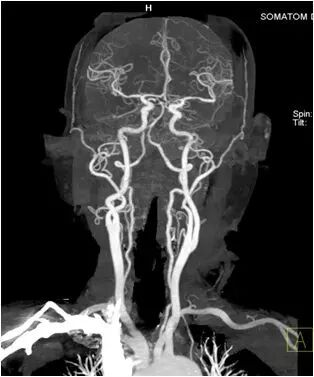

西门子双源CT(SOMATOM Drive)头颈部联合检查,扫描时间不到3秒,所得图像可清晰诊断颈部动脉及颅内动脉疾病。